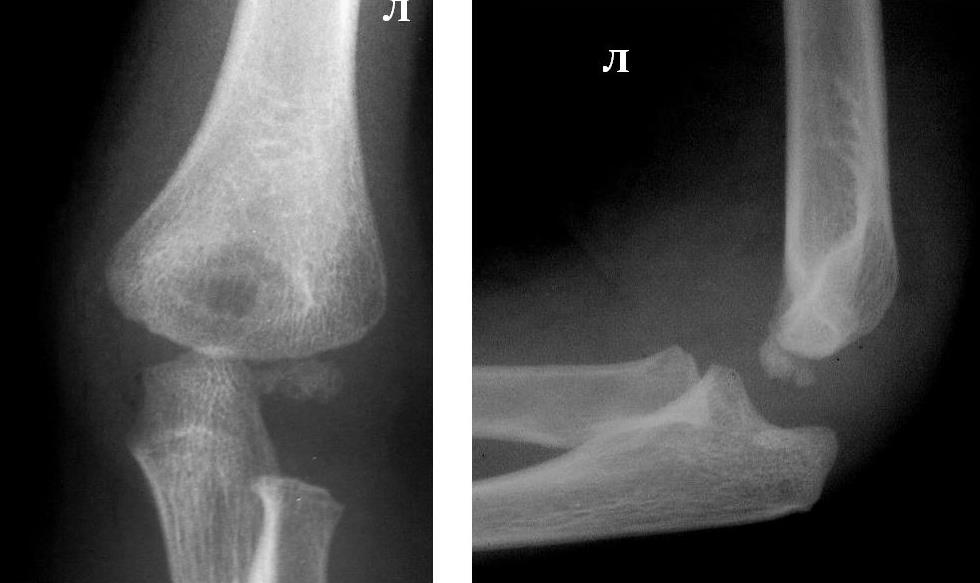

Рентгеновские снимки анкилоза суставов: Как это выглядит